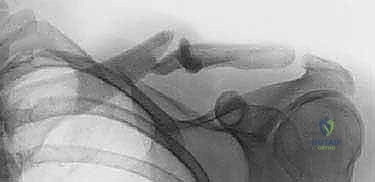

1. الأشعة السينية (X-rays): هي الفحص الأساسي. يتم أخذ صور بوضعيات مختلفة (أمامية خلفية AP، ووضعية زانكا Zanca view التي تميل بزاوية 15-20 درجة للأعلى) لتقييم الكسر بدقة، وتحديد مدى الإزاحة والتقصير.

2. الأشعة المقطعية (CT Scan): في بعض الحالات المعقدة، مثل الكسور المفتتة بشدة، أو الكسور القريبة من المفاصل (الإنسية أو الوحشية)، أو عند الشك في تأثر الأوعية الدموية، يطلب الدكتور هطيف أشعة مقطعية ثلاثية الأبعاد لبناء خطة جراحية دقيقة.